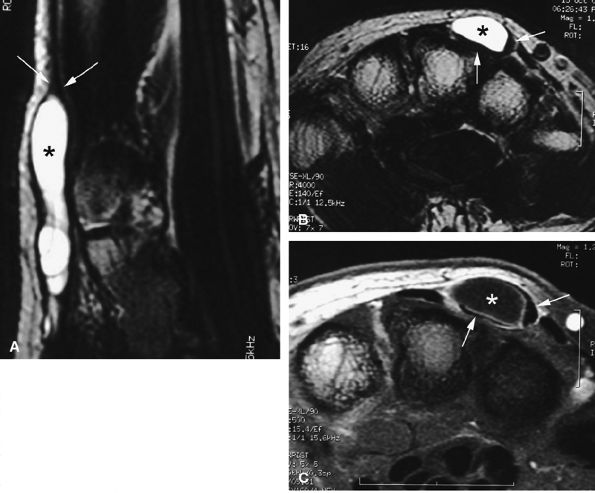

FIGURE 11.67 ● Intraneural ganglion. Axial (A and B) and coronal (C) T1-weighted images of a ganglion (asterisk) infiltrating the medial proper digital nerve (arrows).

|